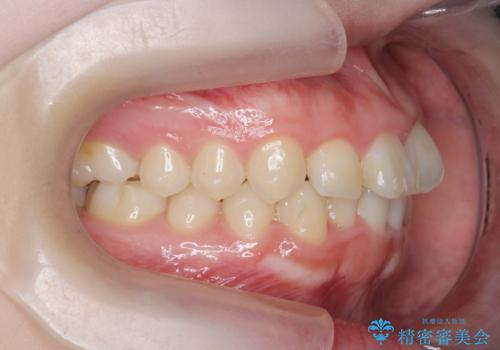

前歯の見た目を改善したい

- ねじれの目立つ前歯の見た目を改善したいと矯正治療を希望され来院されました。

がたつきの改善をマウスピース矯正インビザラインで行っていきます。

ガタつきの改善はもちろん、歯列全体のアーチも放物線状にきれいに排列し審美性を向上させることができました。